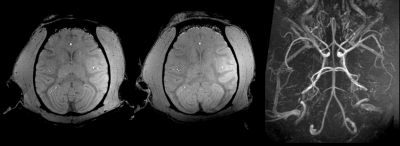

Figure 2 illustrates the quality of the 300-µm and 500-µm isotropic raw GRE and Maximum Intensity Projection images (MIP) of the same images. Figure 3 displays 800-µm T1-weighted MPRAGE images

In vivo MRI data acquired in one macaca rhesus at 11.7 T with 3D GRE sequences. The two images on the left were registered and reconstructed in the transversal plane with 3D multiplanar reformation (MPR) out of 500µm and 300µm isotropic acquisitions. The image on the right side is an MIP made out of the 300µm isotropic gre acquisition. Without any contrast agent enhancement, the images shows a very detailed the animal brain arterial network.